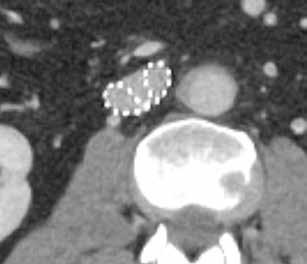

39-jähriger Pat., Z. n. venöser Stent-Anlage bei postthrombotischem Syndrom. Erbitte Gefäßdarstellung zur Stent-Revision. Aquilion PRISM (AiCE) DLP: 833,9 mGy*cm vs. 569,1 mGy*cm Aquilion PRIME (AIDR 3D)

Fall 1:

GIR

Aquilion PRISM (AiCE)

30 // VISIONS 31

Aquilion PRIME (AIDR 3D)